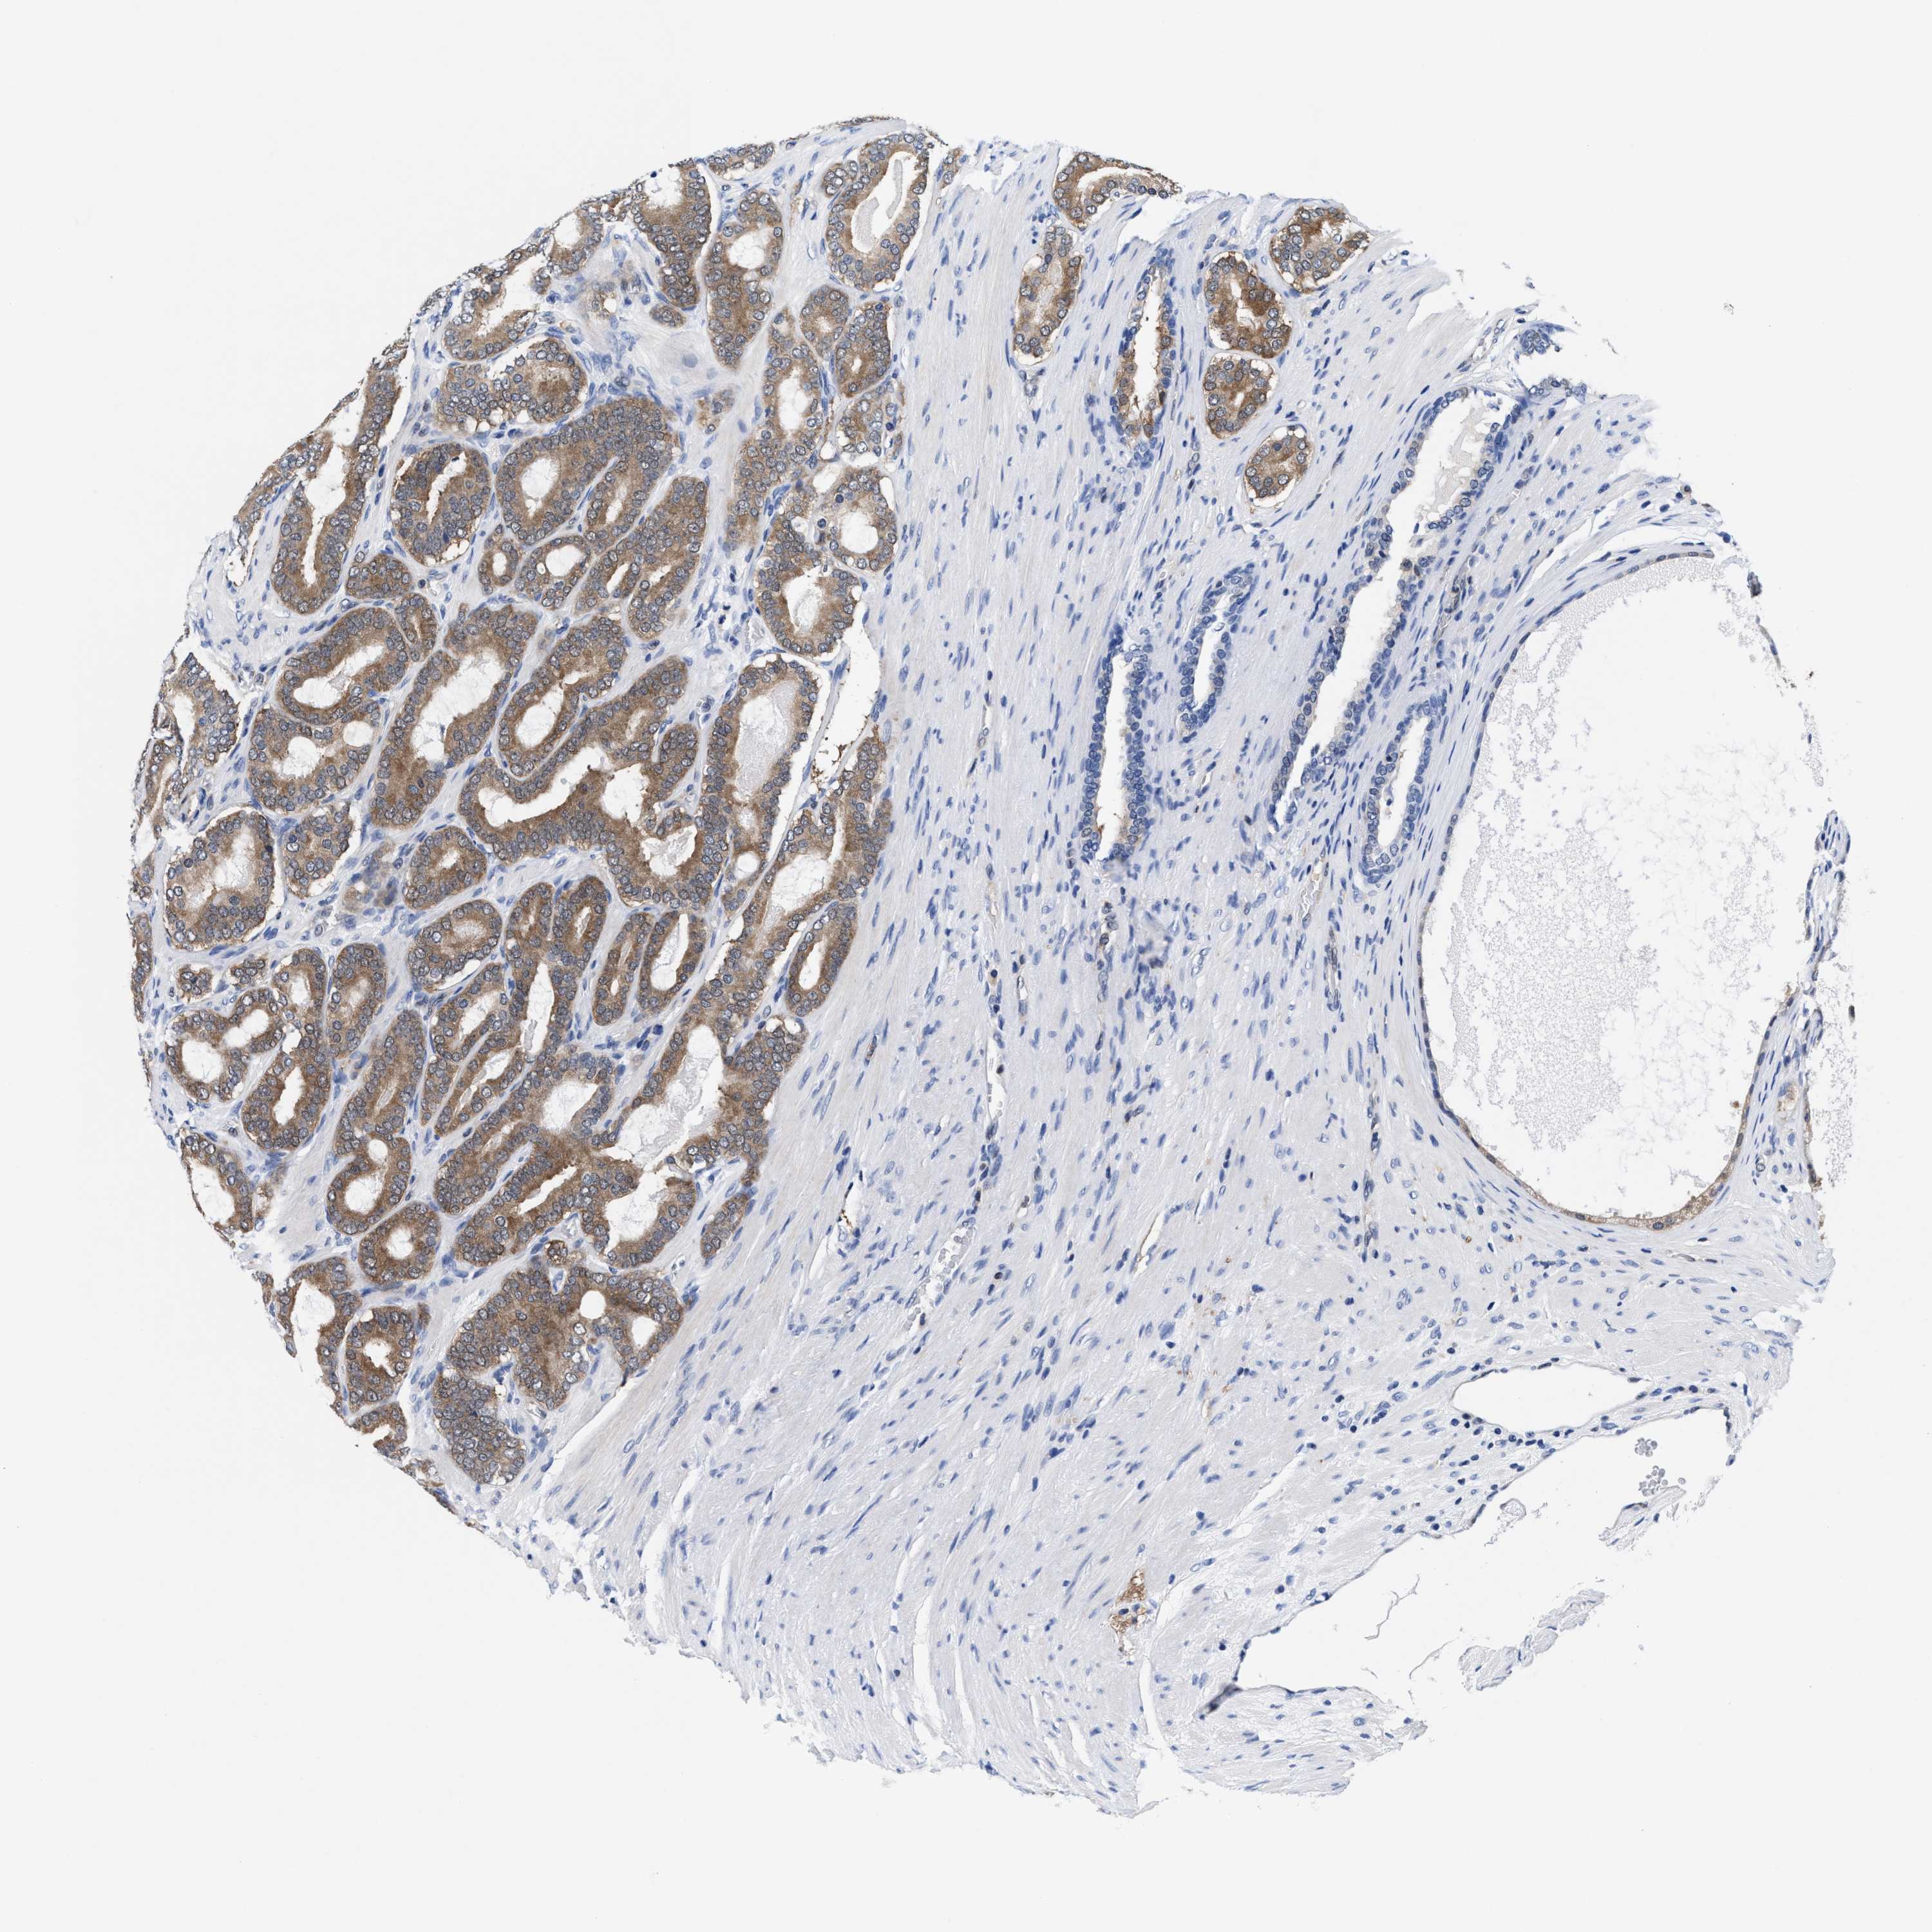

PROSTATE CANCER - Protein expressioni

A mouse-over function shows sample information and annotation data. Click on an image to view it in a full screen mode. Samples can be filtered based on level of antibody staining by selecting one or several of the following categories: high, medium, low and not detected. The assay and annotation is described here.

Antibody stainingi

Antibody staining in the annotated cell types in the current human tissue is reported as not detected, low, medium, or high, based on conventional immunohistochemistry profiling in selected tissues. This score is based on the combination of the staining intensity and fraction of stained cells.

Each image is clickable and will lead to virtual microscopy that enables deeper exploration of all samples and also displays staining intensity scores, fraction scores and subcellular localization as well as patient and tissue information for each sample.

HPA022434

HPA022953

HPA022959

HPA028758

CAB007783

Staining

High

Medium

Low

Not detected

Intensity

Strong

Moderate

Weak

Negative

Quantity

>75%

75%-25%

<25%

None

Location

Nuclear

Cytoplasmic/membranous

Cytoplasmic/membranous,nuclear

Adenocarcinoma, High grade

Adenocarcinoma, Low grade